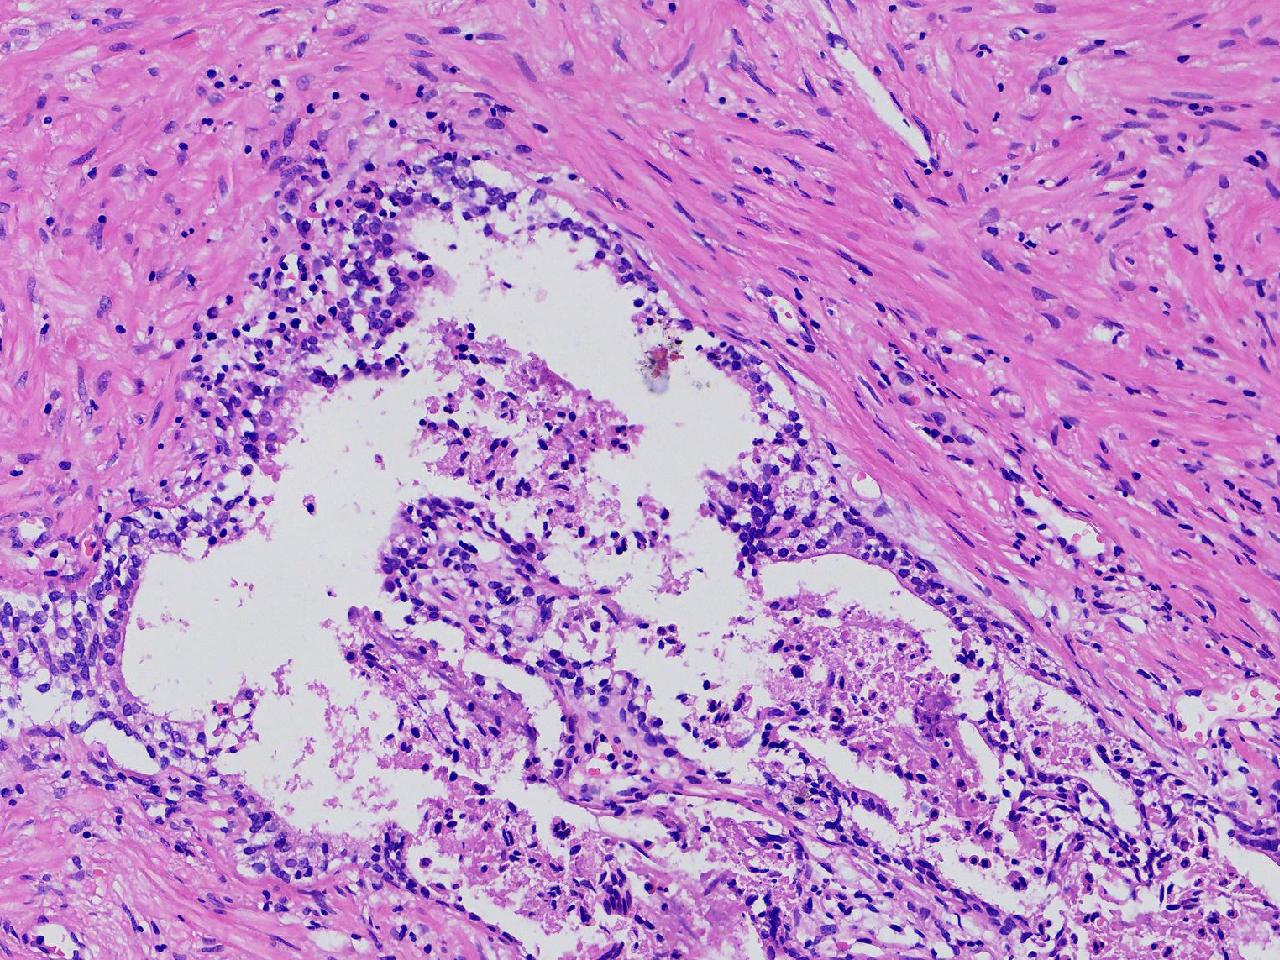

良性前列腺增生?

男,68岁,前列腺电切标本。

前列腺电切标本

灰粉色条索状软组织多块,5X4X3厘米。

前列腺增生。

BPH.